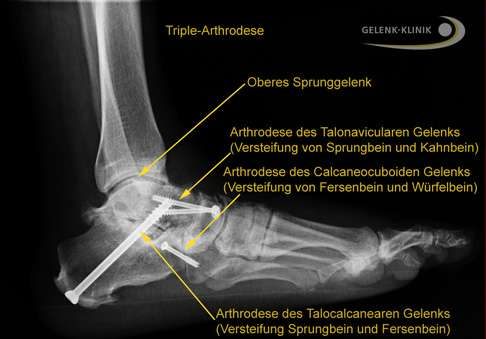

Triple-Arthrodese: 3-fache Versteifung aller Abschnitte des unteren Sprunggelenks:

- talocalcaneares Gelenk (Subtalargelenk) zwischen Sprungbein und Fersenbein

- Talonavikulargelenk zwischen Sprungbein und Kahnbein

- calcaneocuboidales Gelenk zwischen Fersenbein und Würfelbein

Röntgenbild der Triple-Arthrodese aller drei Abschnitte des unteren Sprunggelenks (USG). © Gelenk-Klinik.de

Das Röntgenbild zeigt die vollständige Aufrichtung des Fußlängsgewölbes. Die eingebrachte Platte stabilisiert die innere Säule des Fußgewölbes und unterstützt die Einheilung des eingesetzten Knochenspans. © Gelenk-Klinik.de